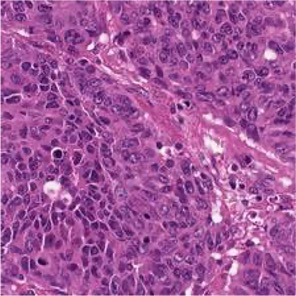

Multiple instance learning (MIL) is a powerful approach to classify whole slide images (WSIs) for diagnostic pathology. A fundamental challenge of MIL on WSI classification is to discover the \textit{critical instances} that trigger the bag label. However, previous methods are primarily designed under the independent and identical distribution hypothesis (\textit{i.i.d}), ignoring either the correlations between instances or heterogeneity of tumours. In this paper, we propose a novel multiplex-detection-based multiple instance learning (MDMIL) to tackle the issues above. Specifically, MDMIL is constructed by the internal query generation module (IQGM) and the multiplex detection module (MDM) and assisted by the memory-based contrastive loss during training. Firstly, IQGM gives the probability of instances and generates the internal query (IQ) for the subsequent MDM by aggregating highly reliable features after the distribution analysis. Secondly, the multiplex-detection cross-attention (MDCA) and multi-head self-attention (MHSA) in MDM cooperate to generate the final representations for the WSI. In this process, the IQ and trainable variational query (VQ) successfully build up the connections between instances and significantly improve the model's robustness toward heterogeneous tumours. At last, to further enforce constraints in the feature space and stabilize the training process, we adopt a memory-based contrastive loss, which is practicable for WSI classification even with a single sample as input in each iteration. We conduct experiments on three computational pathology datasets, e.g., CAMELYON16, TCGA-NSCLC, and TCGA-RCC datasets. The superior accuracy and AUC demonstrate the superiority of our proposed MDMIL over other state-of-the-art methods.